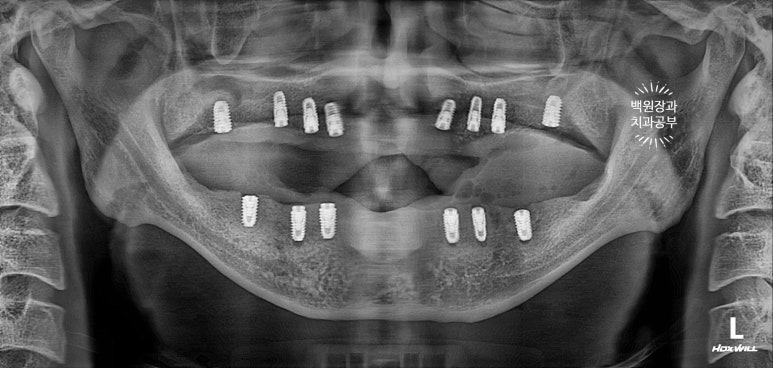

수술 후 촬영한 치과용 파노라마 사진에서 꽤나 예쁘게 심어진 임플란트를 확인할 수 있었습니다.

이렇게 위에는 8개의 임플란트가, 아래에는 6개의 임플란트가 예쁘게 식립된 것을 보실 수 있을겁니다.

깔끔하게 완성된 보철물은 치과용 파노라마 사진에서 확인하실 수 있고,

비전공자가 보아도 나란히 가지런한 임플란트는 편안함을 줍니다.

똑같아 보일 수 있으시겠지만, 6개월이 지난 후 치과용 파노라마 사진입니다.

보통 임플란트의 초기 실패는 6개월 정도 안에 발견할 수 있기에, 이 시기에 한 번 더 오셔서 체크해보는 것이 중요합니다.